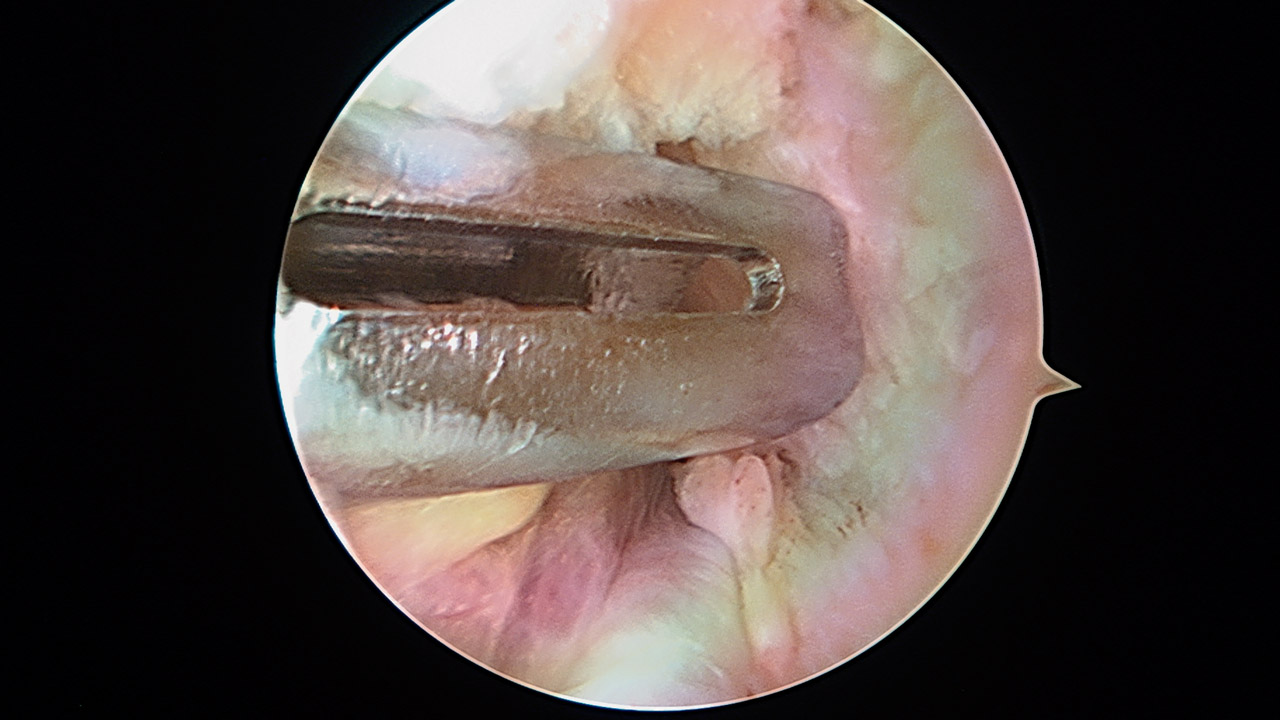

Paso 6: sutura del ligamento glenohumeral inferior

Una vez realizada la fijación del aloinjerto, se procede a la sutura de los 2 anclajes (Figura 12), con lo que se cierra el suelo de la articulación.